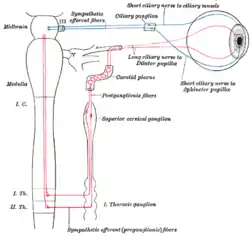

Pupillary response is a physiological response that varies the size of the pupil, via the optic and oculomotor cranial nerve.

A constriction response (miosis),[1] is the narrowing of the pupil, which may be caused by scleral buckles or drugs such as opiates/opioids or anti-hypertension medications. Constriction of the pupil occurs when the circular muscle, controlled by the parasympathetic nervous system (PSNS), contracts, and also to an extent when the radial muscle relaxes.

A dilation response (mydriasis), is the widening of the pupil and may be caused by adrenaline; anticholinergic agents; stimulant drugs such as MDMA, cocaine, and amphetamines; and some hallucinogenics (e.g. LSD).[2] Dilation of the pupil occurs when the smooth cells of the radial muscle, controlled by the sympathetic nervous system (SNS), contract, and also when the cells of the iris sphincter muscle relax.

The responses can have a variety of causes, from an involuntary reflex reaction to exposure or inexposure to light—in low light conditions a dilated pupil lets more light into the eye—or it may indicate interest in the subject of attention or arousal, sexual stimulation,[3] uncertainty,[4] decision conflict,[5] errors,[6] physical activity[7] or increasing cognitive load[8] or demand. The responses correlate strongly with activity in the locus coeruleus neurotransmitter system.[9][10][11] The pupils contract immediately before REM sleep begins.[12] A pupillary response can be intentionally conditioned as a Pavlovian response to some stimuli.[13]